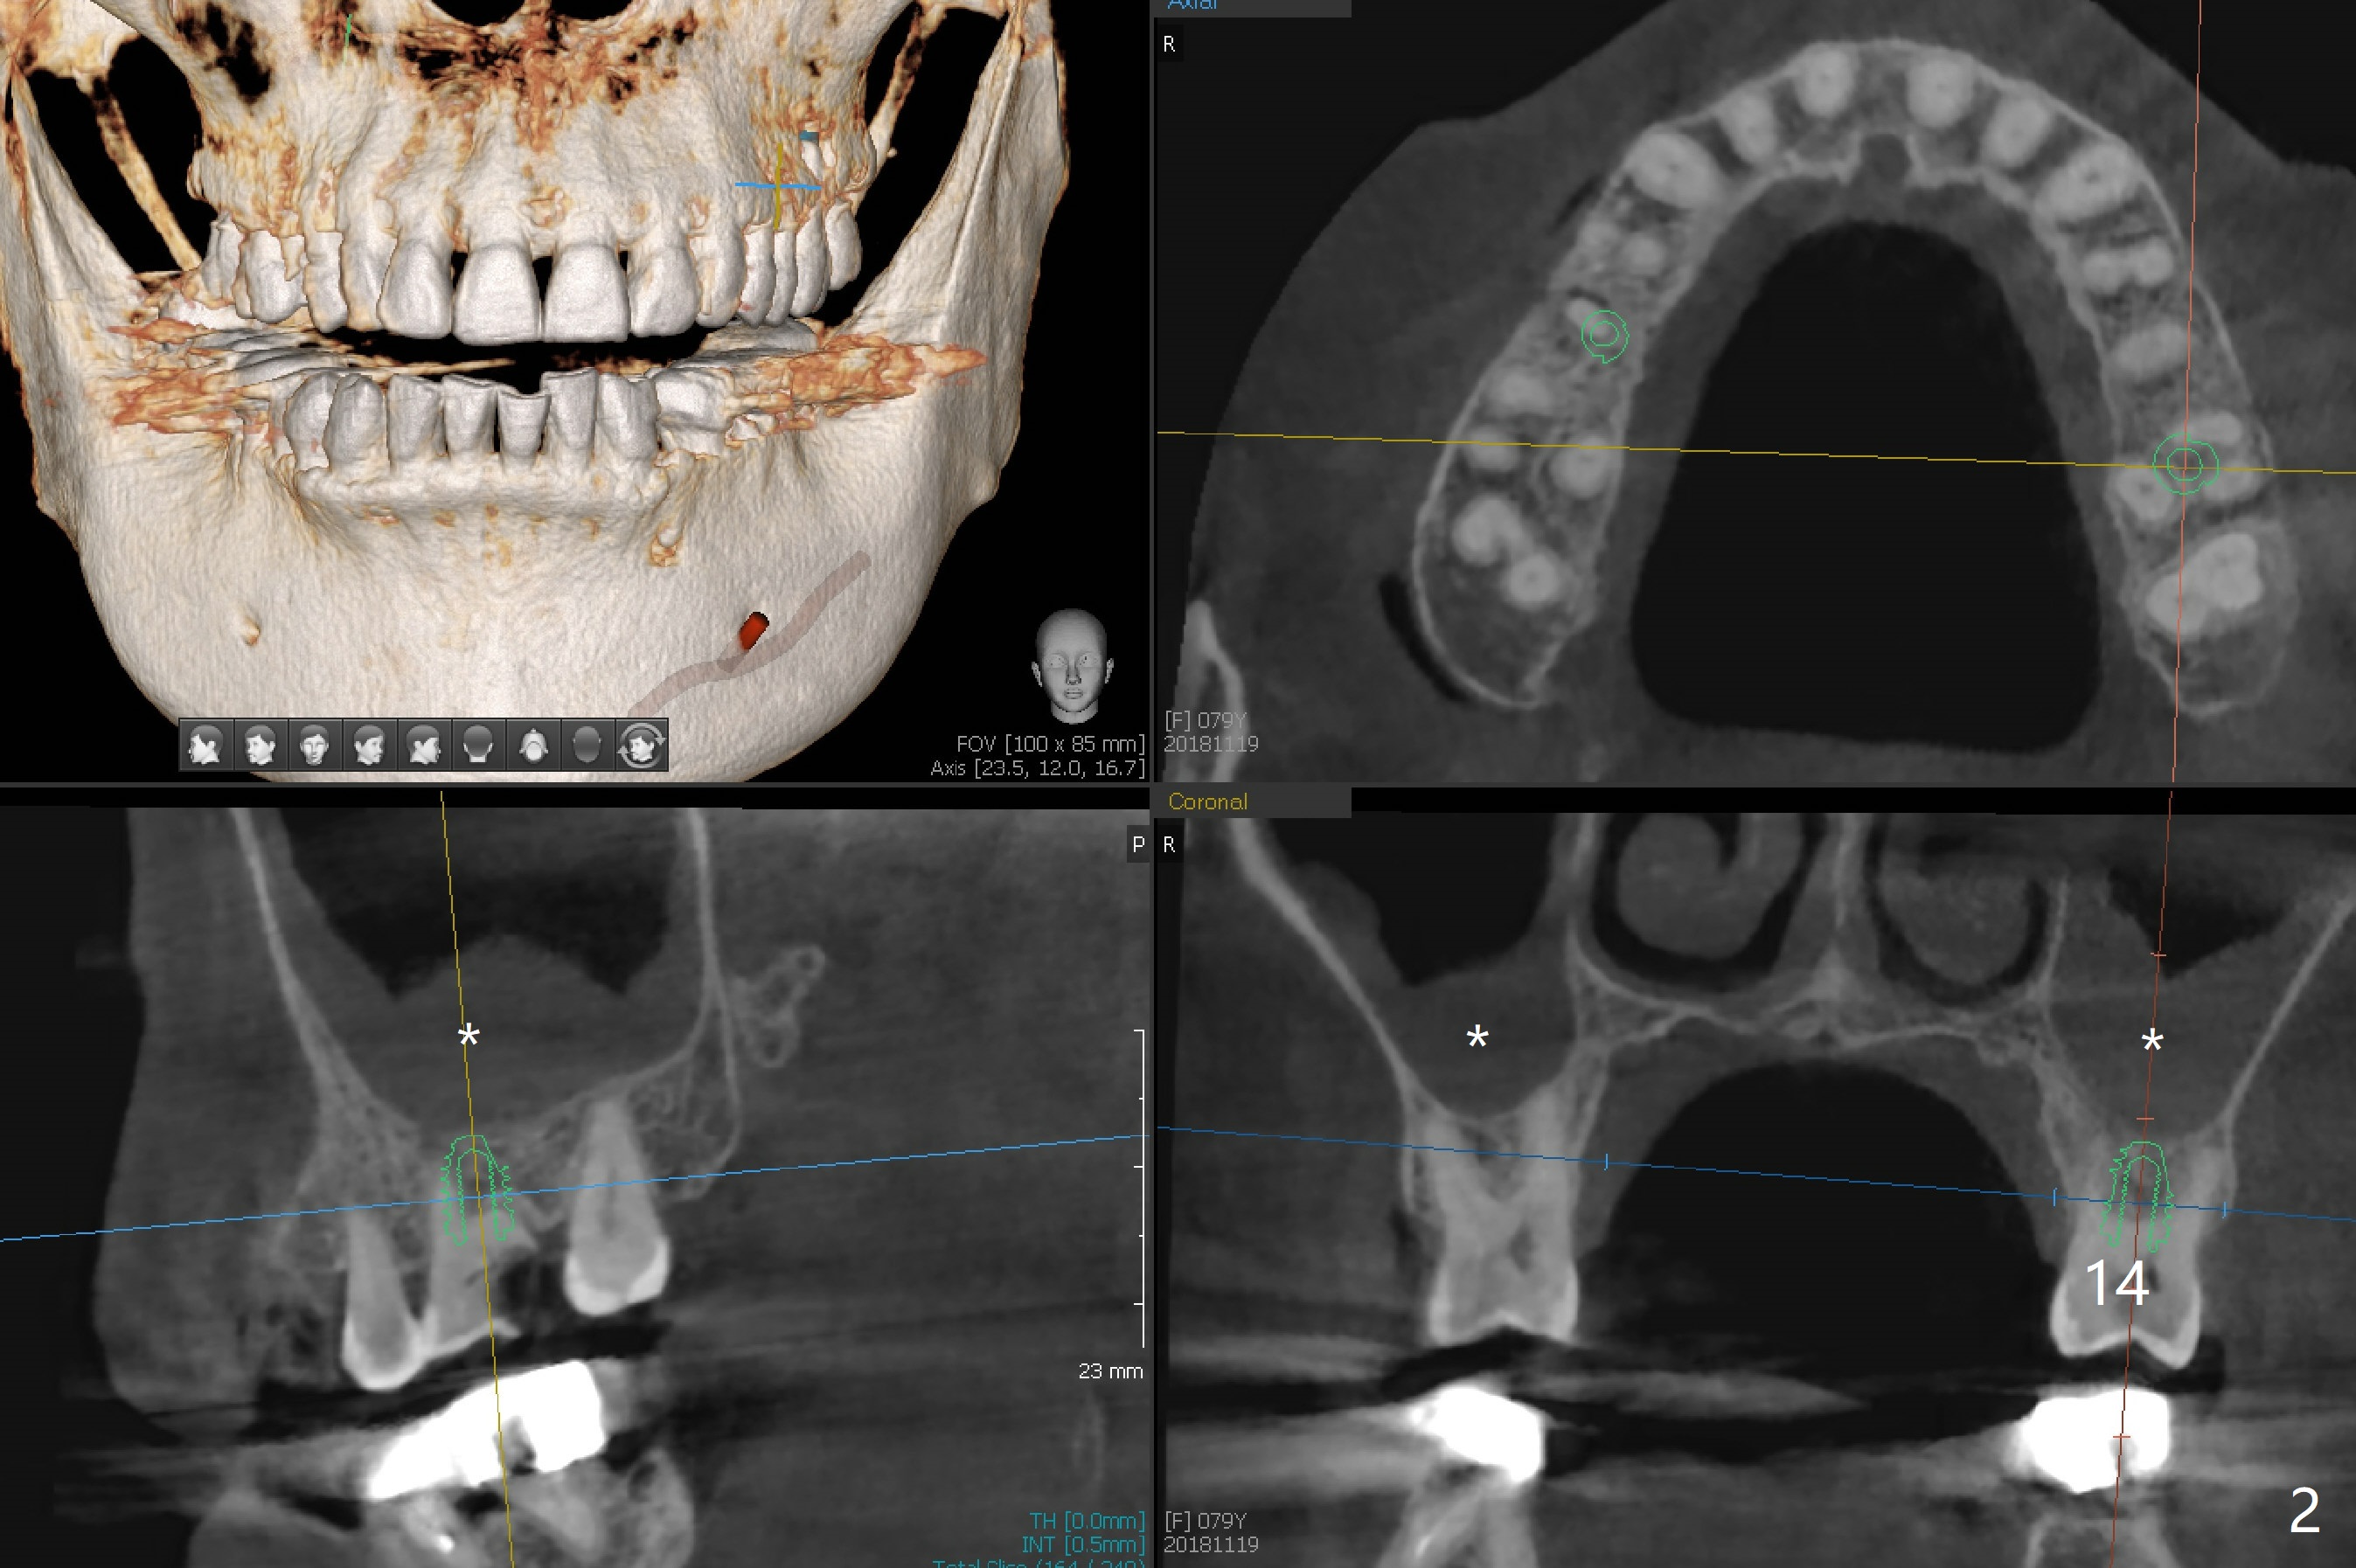

A 79-year-old woman has subgingival symptomatic caries at #14 and residual roots at #4 and 21 (Fig.1). Because of bilateral thick sinus membrane (Fig.2 *) with nasal obstruction, immediate implants at #14 and 4 will be placed without sinus lift (Fig.3,4). To obtain primary stability, a long implant will be placed at #21 (15 or 16 mm), while a narrower implant (3 mm 1-piece, Fig.6)) is safer than 3.8 mm one (2-piece, Fig.5) in term of preventing periimplantitis (buccal thread exposure). Impression has been taken for guide at #14.